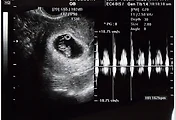

장안동의 린산부인과를 다녀왔다.

몸이 좀 이상하다고 하기에 지난주 금요일 임신테스트기를 통해 테스트를 했는데 정확히 두 줄.

주위사람들이 임신테스트 후 바로 산부인과에 가면 임신 일수가 얼마 되지 않아 애기집이 안보인다고 좀 늦게 가는것을 권했다. 그 얘길 듣고 1주일 정도 늦쳐서 갔는데 벌써 7주가 지났다고 한다. 많이 자랐다고^^. 의사선생님도 조금 늦게온게 잘한거라고 말씀하시고... 일찍가면 병원을 한두번 더 가야한다는.

심장뛰는 소리도 듣고 머리며 팔이며 얘기를 해주는데 어찌나 신기하고 감동스럽던지.

예정일은 5월 초순. 2주 후에 좀더 정확히 알려준다고 한다.